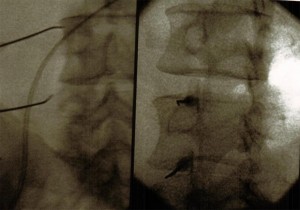

TÉCNICA

Paciente en decúbito prono, con una almohada en abdomen para disminuir la lordosis fisiológica. Con el arco de fluoroscopia en en posición AP  se localiza el espacio a tratar y con un marcador radiopaco se localiza y señala en la piel el punto de punción. Se moviliza el arco de rayos en dirección cráneo-caudal para eliminar el doble contorno. Se prepara la zona de punción con antiséptico, y se infiltra la piel, el tejido celular subcutáneo y los planos musculares con anestésico local. Se realiza la inyección con una  aguja de Tuohy hacia el target desde 2 cuerpos vertebrales inferiores al nivel de entrada en el espacio epidural. Se localiza el espacio epidural con la técnica de pérdida de resistencia y se inyecta contraste radiológico en visión directa (epidurograma). A continuación se coloca el arco de fluoroscopia en  en posición lateral para comprobación de la correcta colocación de la aguja y distribución del contraste. Se vuelve el arco de fluoroscopia a la posición anteroposterior y se inyecta la medicación (anestésicos locales y esteroides).